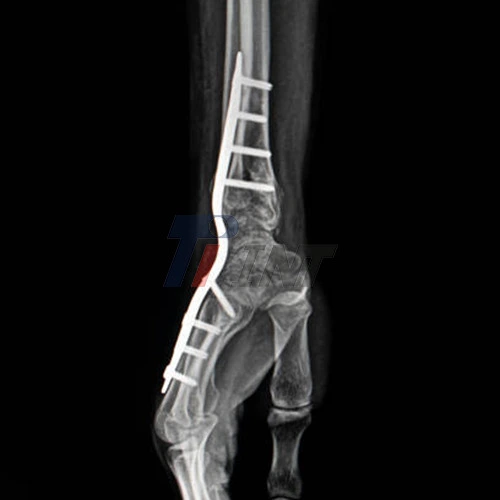

Wrist surgery involving titanium plates is a common procedure for treating severe fractures or other wrist injuries. If you're scheduled for this type of surgery or have recently undergone it, you might be wondering what lies ahead. This comprehensive guide will walk you through the recovery process, potential complications, and long-term expectations for titanium plate in wrist surgery.

You may experience some stiffness or aching in your wrist, especially when attempting new movements or activities. This is normal and usually improves with time and continued therapy. However, if you experience sharp pain or a significant increase in discomfort, it's important to consult your healthcare provider. As your recovery progresses, you'll likely have periodic follow-up appointments with your surgeon. These visits may include X-rays to ensure the bones are healing correctly around the titanium plate. Your surgeon will use these appointments to assess your progress and adjust your recovery plan as needed.